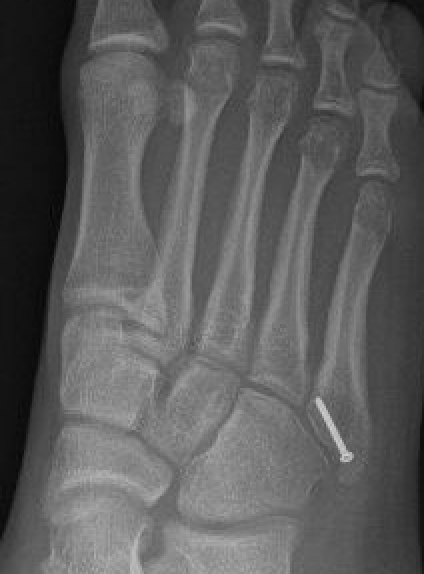

Xray

Zone 2 fractures

Union of zone 2 fracture with nonoperative care

Progression to nonunion of zone 2 fracture with nonoperative care

Zone 3 Fractures

Progression to nonunion of zone 3 fracture with nonoperative care

Displaced fracture Nonunion